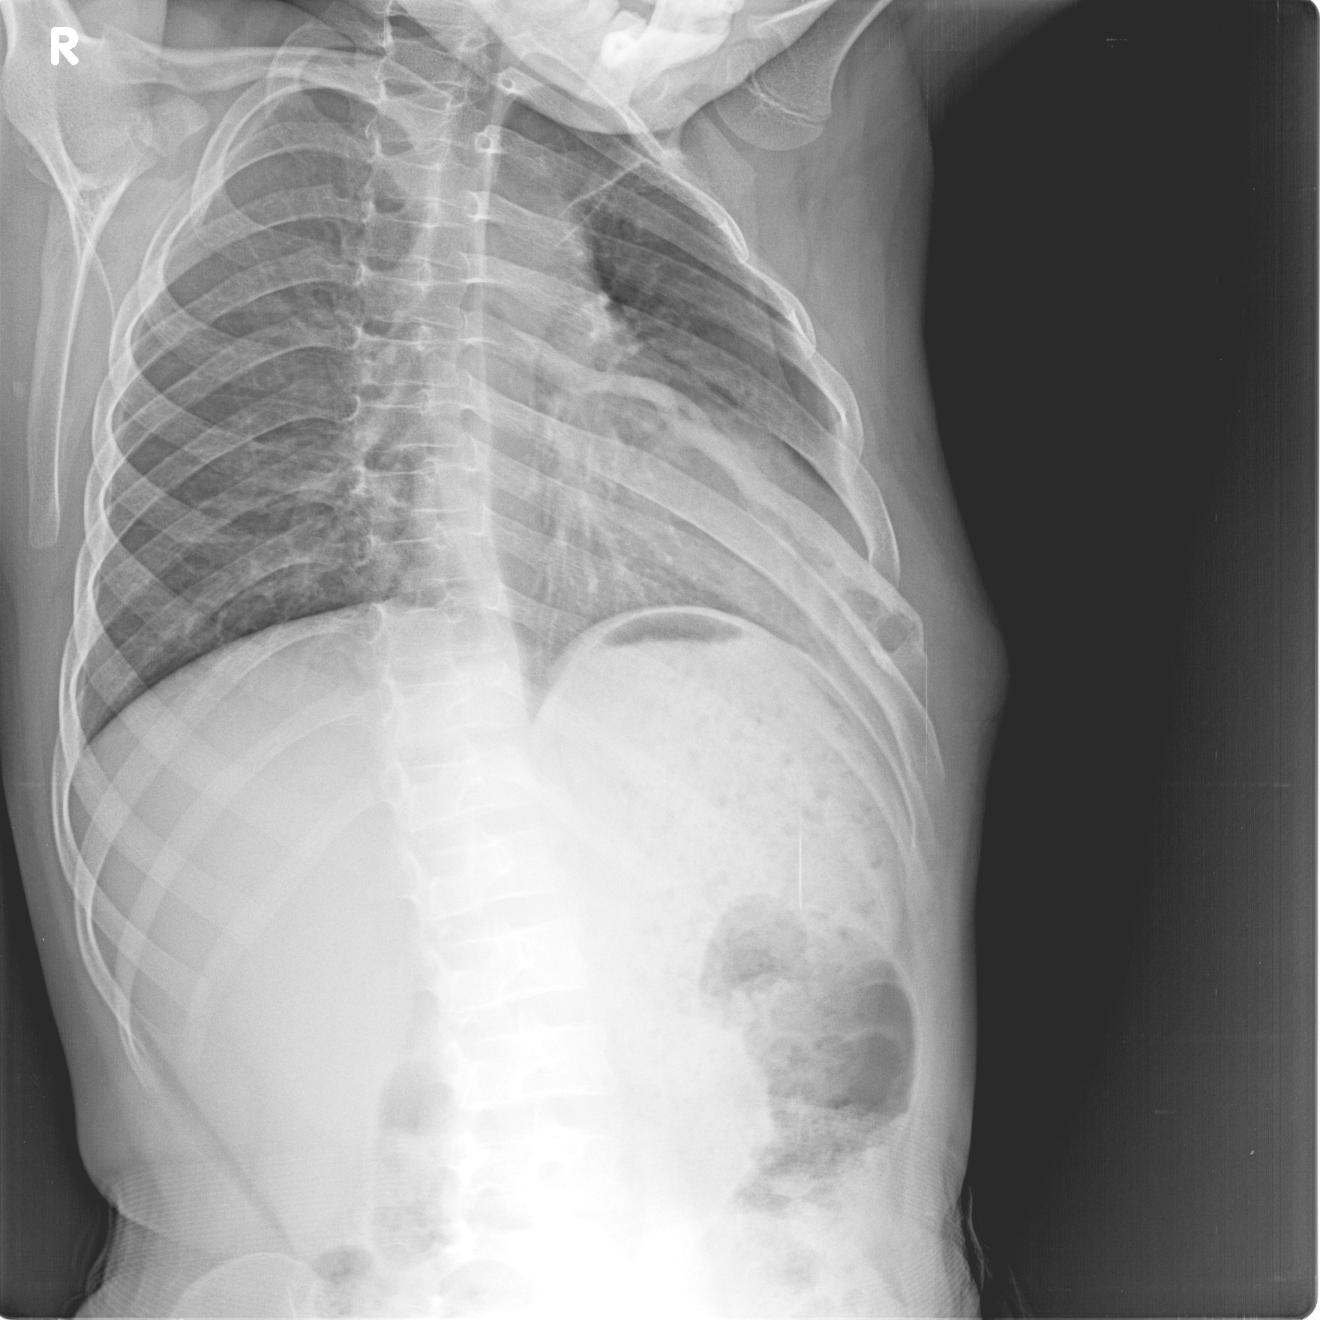

标题: PED0927:男 10y 胸廓隆起 近10天感觉有点疼 [打印本页]

标题: PED0927:男 10y 胸廓隆起 近10天感觉有点疼

追问无其他病史

考虑左侧第6肋肋腋骨质呈膨胀性破坏.后缘骨皮质破坏,髓腔变窄.左外胸壁软组织肿胀.考虑结核可能性大.骨肿瘤不除.